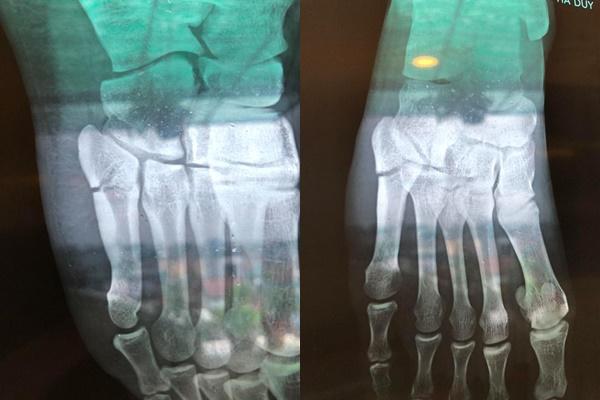

Mới đây, cựu diễn viên đình đám một thời Hà Duy khiến người quan tâm lo lắng khi tiết lộ về tình trạng sức khỏe của mình. Theo chia sẻ của con trai NSƯT Hương Dung thì anh bị ngã. Sau khi đi khám và chụp chiếu, bác sĩ chẩn đoán anh bị gãy xương bàn chân phải. Hiện tại, Hà Duy đang được điều trị bằng phương pháp bó lá.